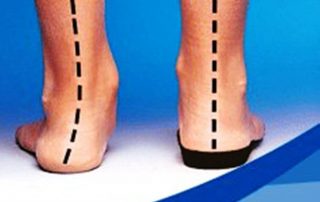

Leg Length Discrepancy (LLD) and Pain

I had this Leg Length Discrepancy since I was a toddler with chronic knee pain that would wake me from my sleep. The only relief was to run scolding hot water in the bathtub over my knee until I would [...]